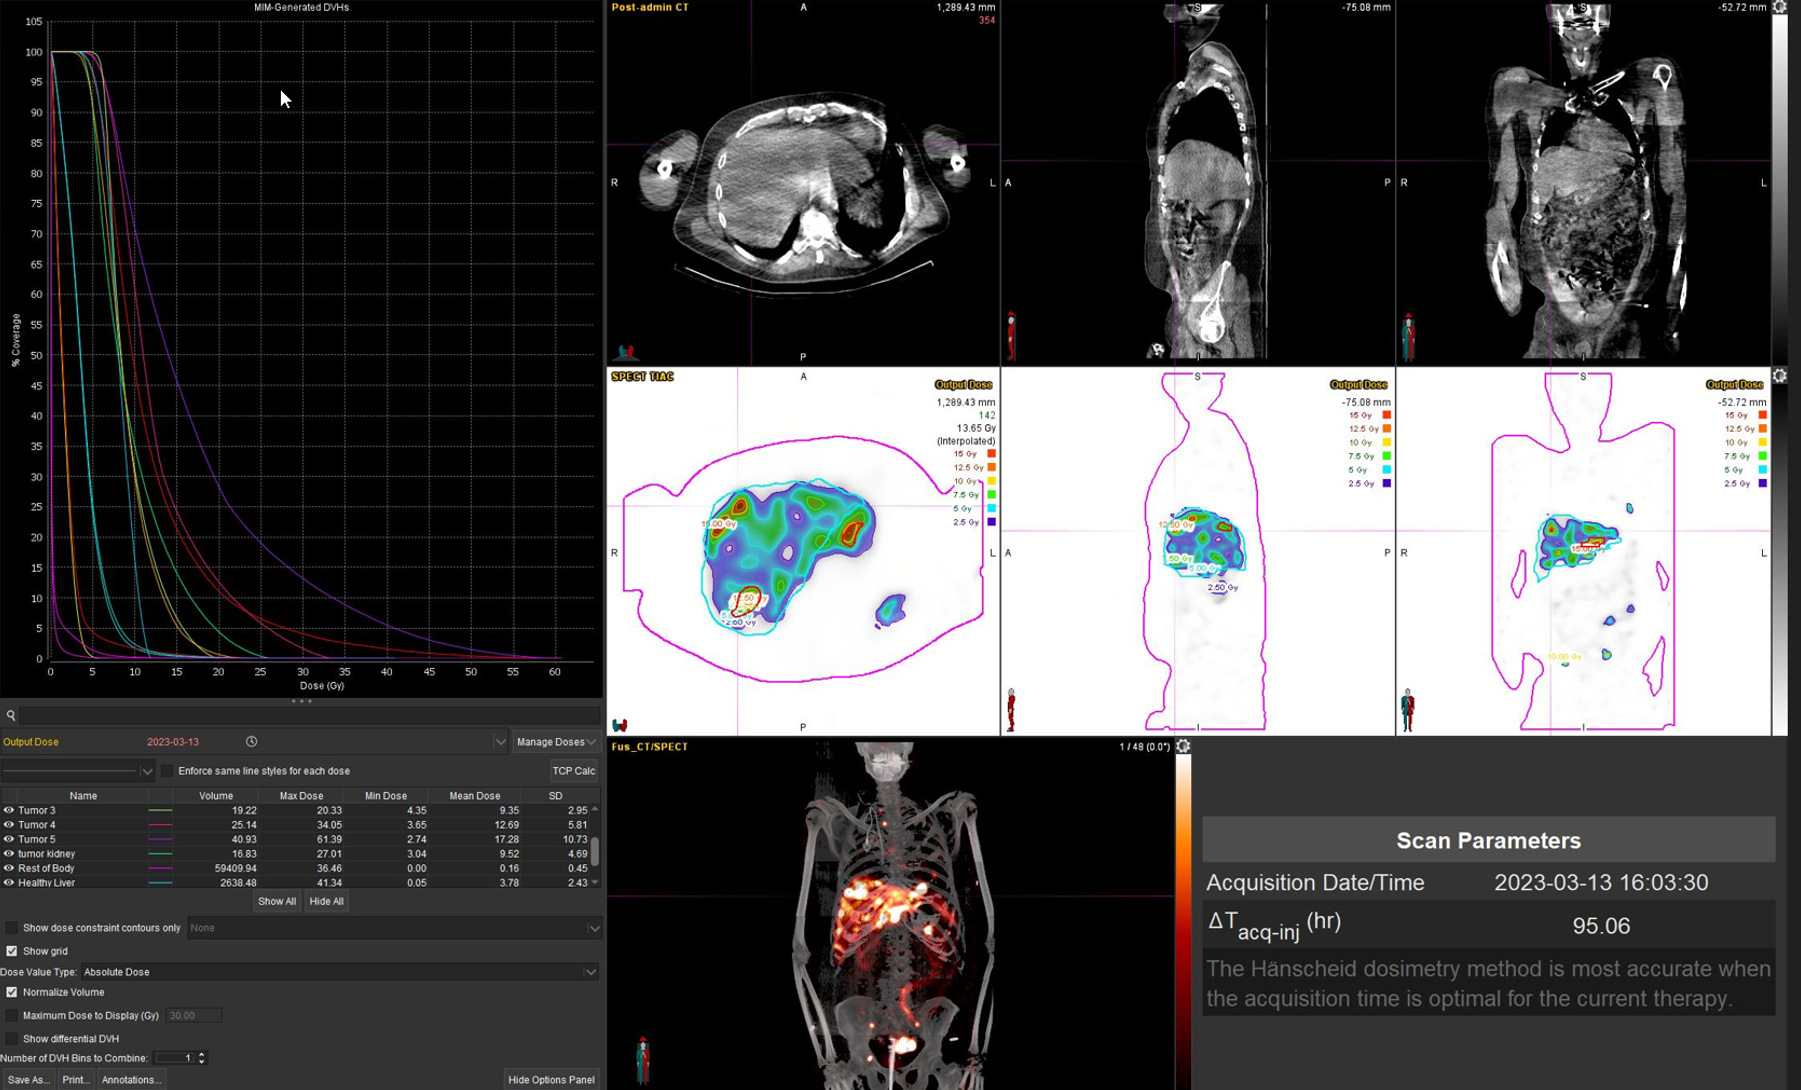

Η θεραπεία με Lu-177 DOTATATE (PRRT – Peptide Receptor Radionuclide Therapy) αποτελεί μια από τις πλέον εξελιγμένες μορφές στοχευμένης ραδιονουκλιδικής θεραπείας για νευροενδοκρινείς όγκους του γαστρεντερικού και του παγκρέατος, αξιοποιώντας την υπερέκφραση των υποδοχέων σωματοστατίνης στους νεοπλασματικούς ιστούς. Η διαδικασία περιλαμβάνει τον ακριβή προσδιορισμό της έκτασης της νόσου μέσω Ga68 DOTATATE PET/CT, την επιβεβαίωση υψηλής έκφρασης υποδοχέων SSTR και στη συνέχεια τη χορήγηση του Λουτέσιο-177 DOTATATE, το οποίο δεσμεύεται εκλεκτικά στους ανωτέρω υποδοχείς. Η ενέργεια του β-εκπομπού Λουτέσιου επιτρέπει στοχευμένη κυτταροτοξική δράση μέσα στον όγκο, με ελάχιστη διασπορά σε υγιείς ιστούς. Η σύγχρονη πρακτική ενσωματώνει ειδικά λογισμικά δοσιμετρίας, που υπολογίζουν την απορροφούμενη δόση σε κρίσιμα όργανα (ήπαρ, νεφροί, μυελός) και την πραγματική δόση στον όγκο, επιτρέποντας εξατομικευμένο σχεδιασμό και βελτιστοποιημένη θεραπευτική στρατηγική. Μετά από κάθε κύκλο θεραπείας πραγματοποιείται απεικονιστικός έλεγχος, αξιολόγηση τοξικοτήτων και συνολική εκτίμηση ανταπόκρισης, καθοδηγώντας τις επόμενες φάσεις της θεραπείας. Το Lu-177 DOTATATE έχει αποδειχθεί εξαιρετικά αποτελεσματικό στη σταθεροποίηση και συχνά στη συρρίκνωση της νόσου, παρατείνοντας την επιβίωση και βελτιώνοντας σημαντικά την ποιότητα ζωής των ασθενών.

Η αξία της μεταθεραπευτικής δοσιμετρίας

Με τη SPECT‑CT ποσοτικοποίηση υπολογίζουμε απορροφούμενες δόσεις σε όγκους και όργανα‑στόχους (νεφροί, σιελογόνοι, ήπαρ, μυελός κ.ά.). Αυτό: